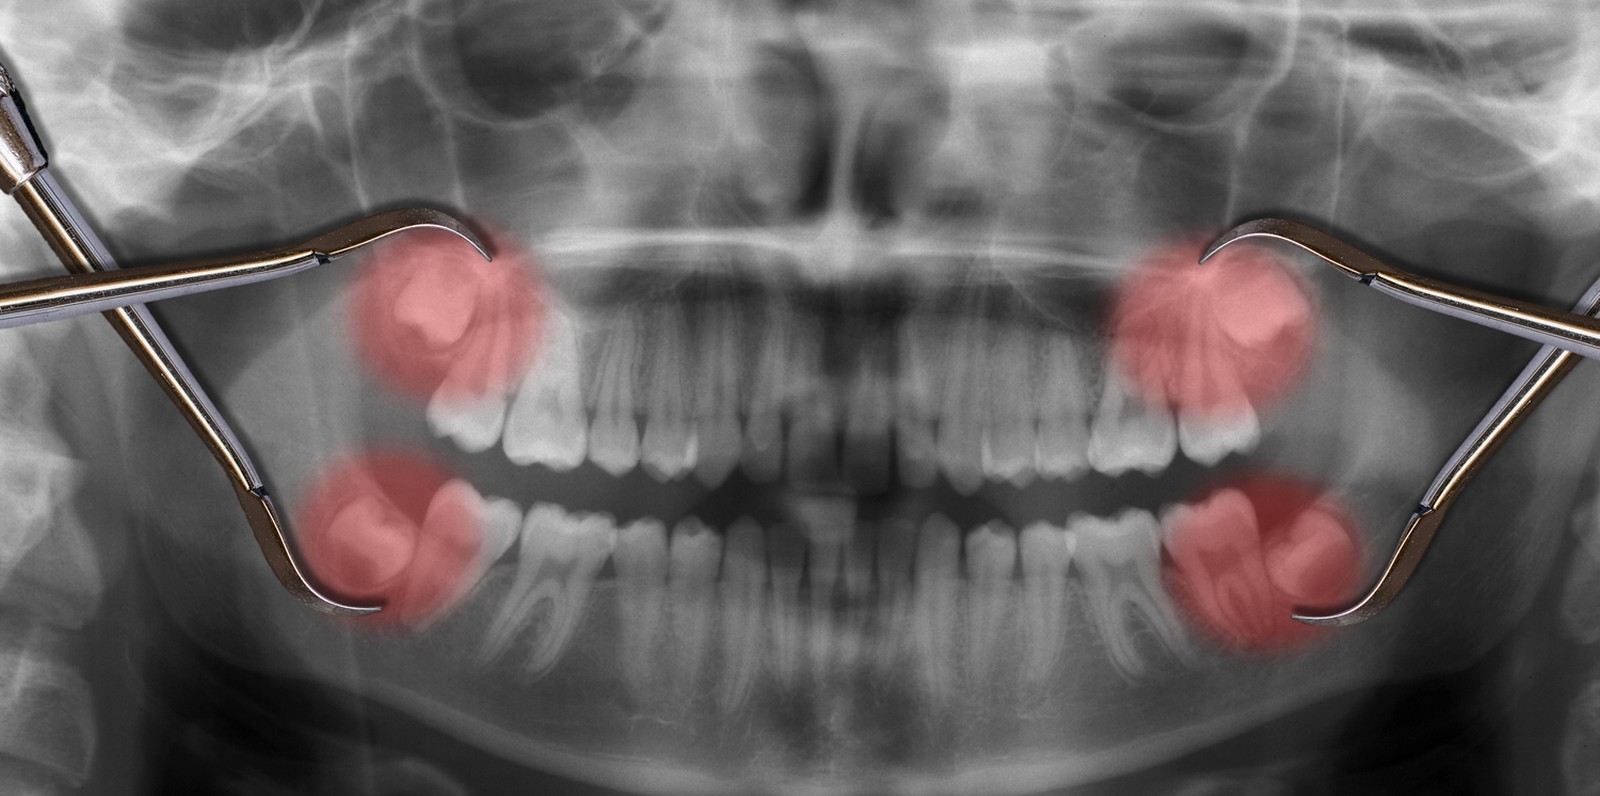

Your dentist will ask you to have an X-ray before having a wisdom tooth removed, so they can see the exact position of the tooth in the gum. This will allow your dentist to work out the best way to perform the extraction of wisdom teeth. Often, wisdom tooth removal is a straightforward procedure that your dentist will be able to do at the dental practice, under local anaesthesia.